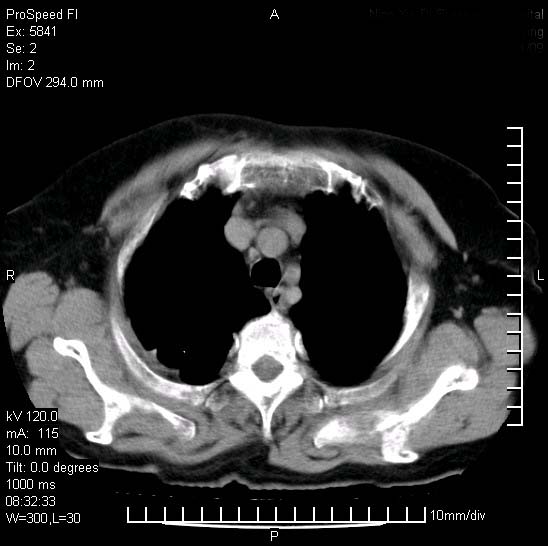

胸痛,咳嗽,气短一周,无发热。右上肺见一结节灶,边缘刺角,内见多个小钙化结节。考虑结核球?肿瘤? 余无异常没有上传。

考虑右肺上叶继发性肺结核,结核球形成。

胸膜是受侵的,考虑感染,结核球可能性大

考虑结核球,并胸膜局限性增厚!!